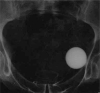

Introduction: Artificial urinary sphincter (AUS) implantation is the treatment of choice for male urinary incontinence (UI). The aim of the present study was to evaluate treatment outcomes of UI in men using an AUS with a cuff placed around the prostatic urethra.

Material and methods: Forty-three men with preserved prostatic urethra were selected for AUS implantation due to UI. Twenty patients had the cuff implanted around the prostate using the retropubic approach (Group 1), and 23 had the cuff placed around the bulbous urethra (Group 2). Both groups were compared in terms of continence quality as well as intra- and postoperative complications.